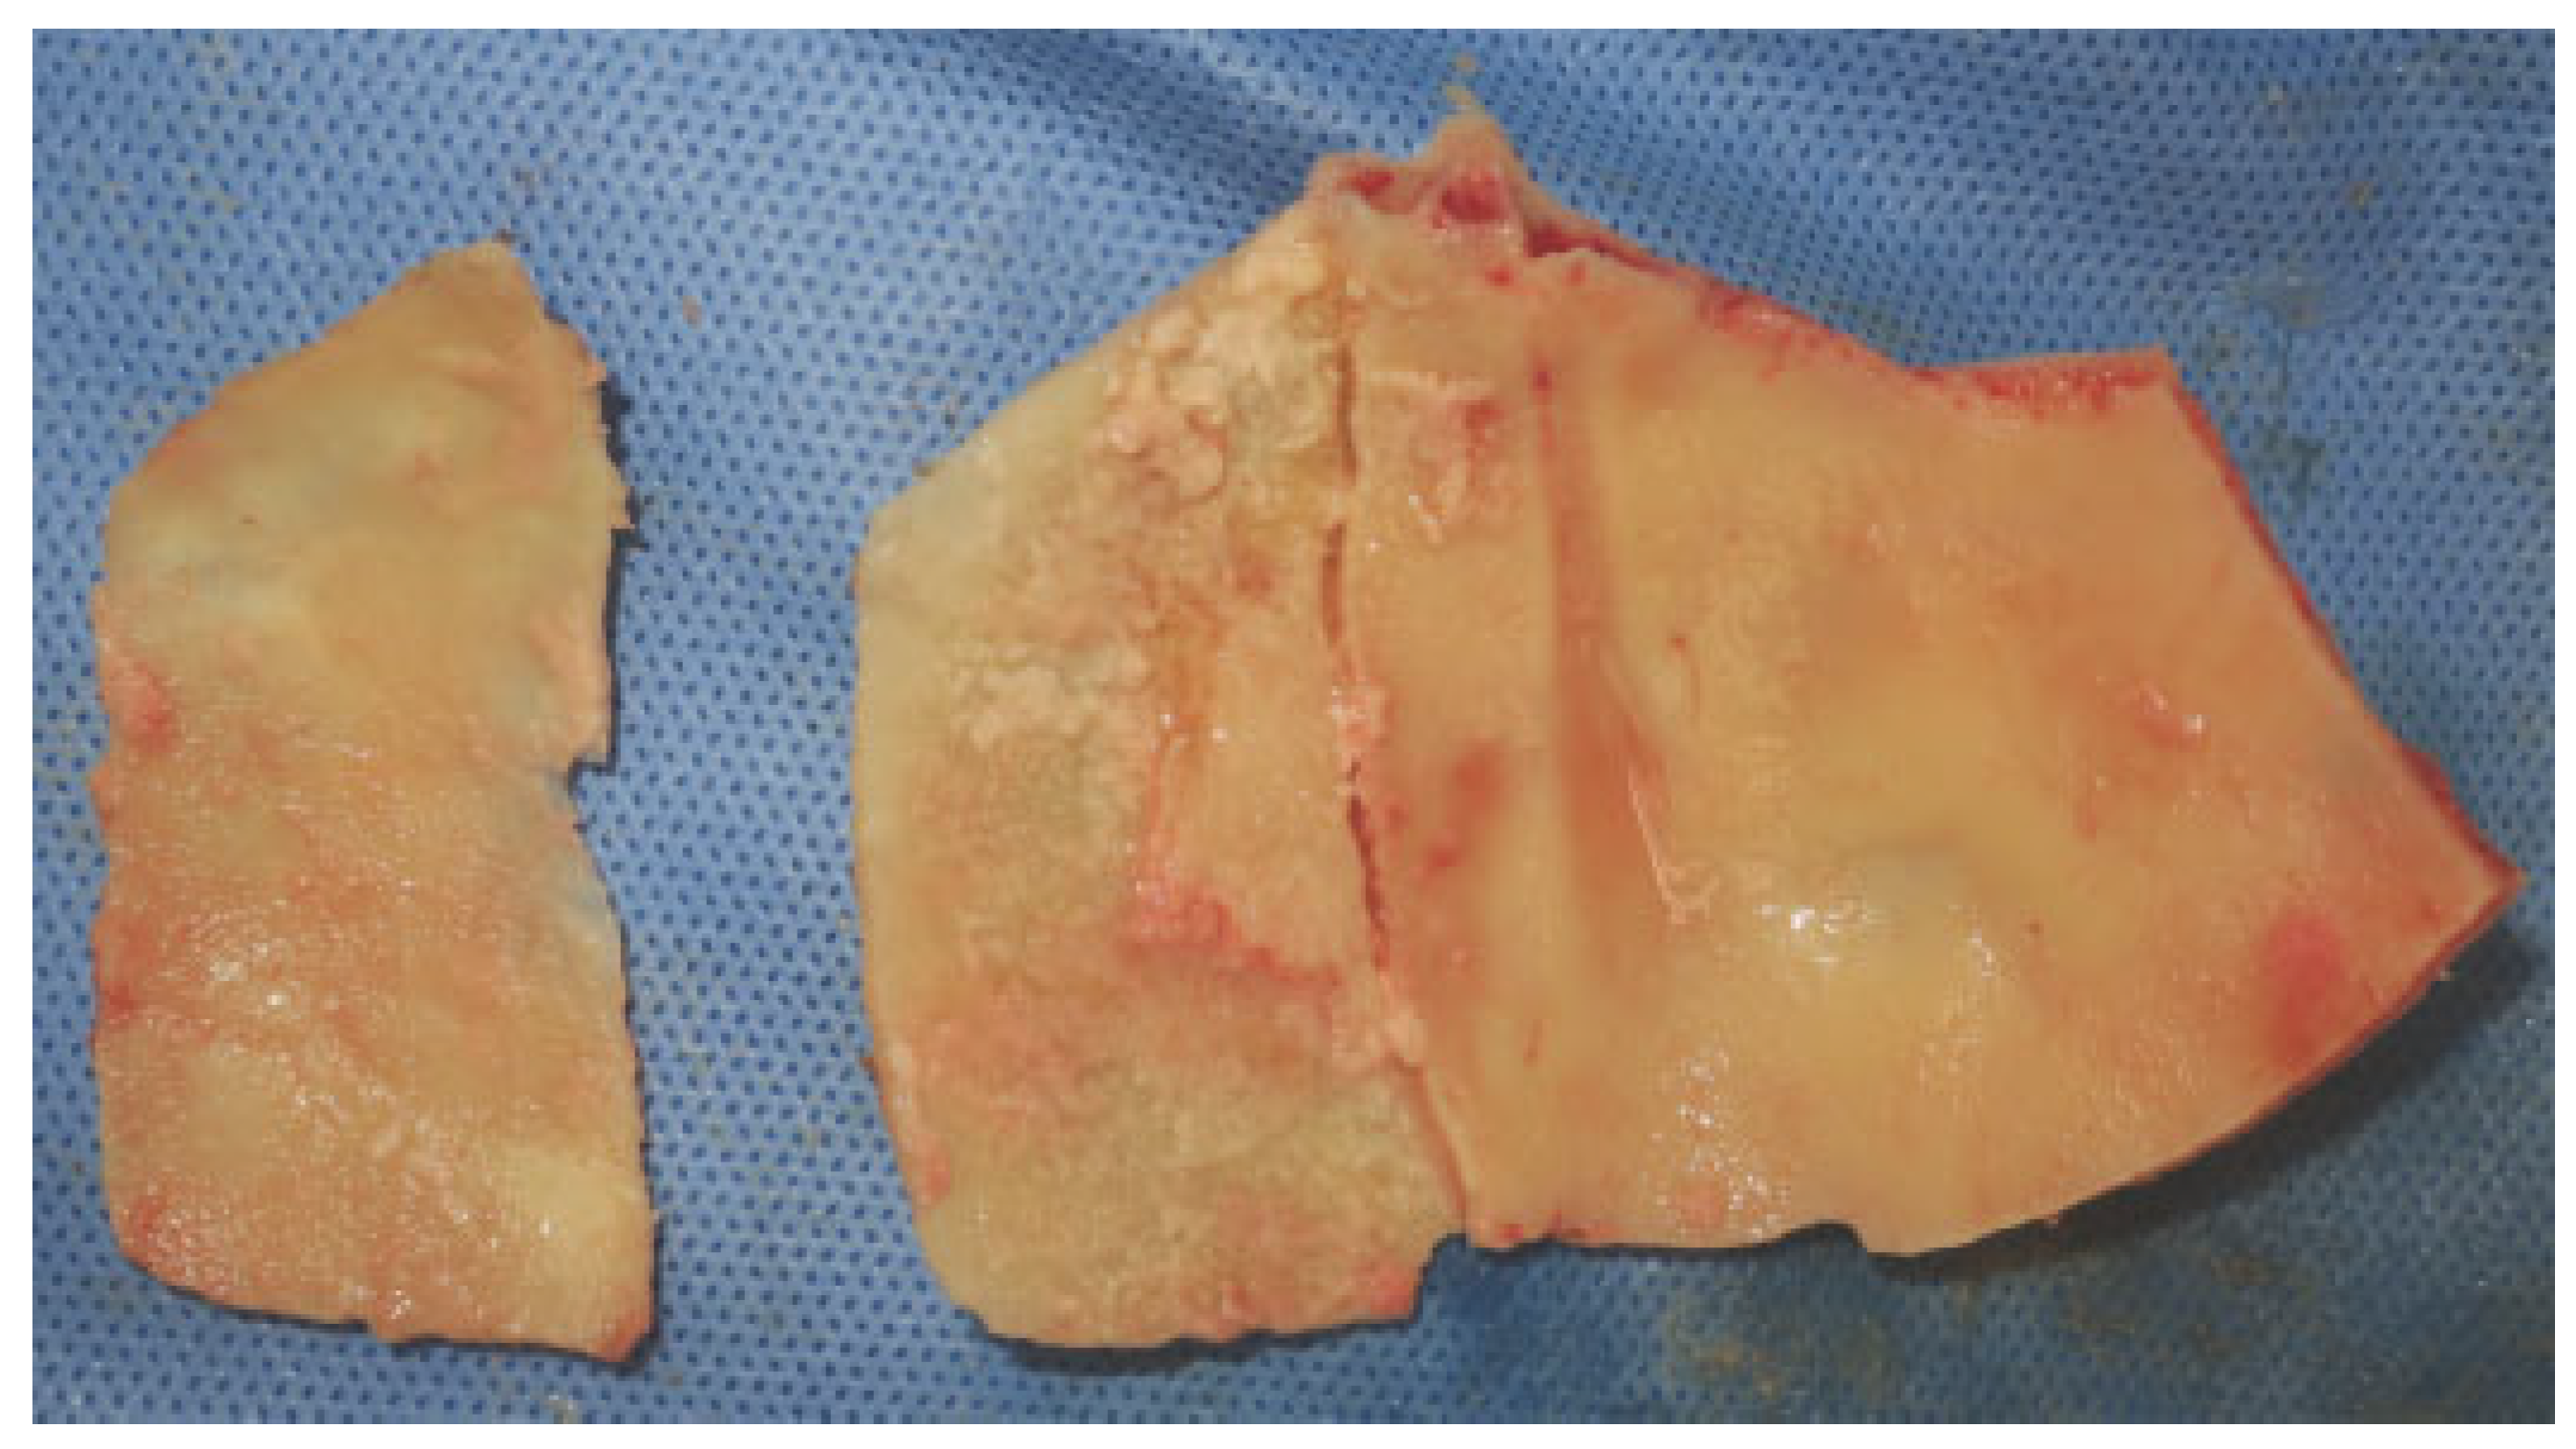

In cases of severe comminution, bony loss, and instability, reconstruction of the anterior table can be done with auto- genous bone graft. There are several sources for nonvascu- larized autologous bone graft including calvarium, ribs, ilium, temporal fossa, and patella.[23,24] Free rib grafts have been shown to partially resorb, thus leading to secondary deformities. Although iliac bone has been used extensively in the past, at present most surgeons prefer split calvarial bone graft[25] (Figure 6).

Figure 6. Intraoperative view of a split calvarial bone graft.